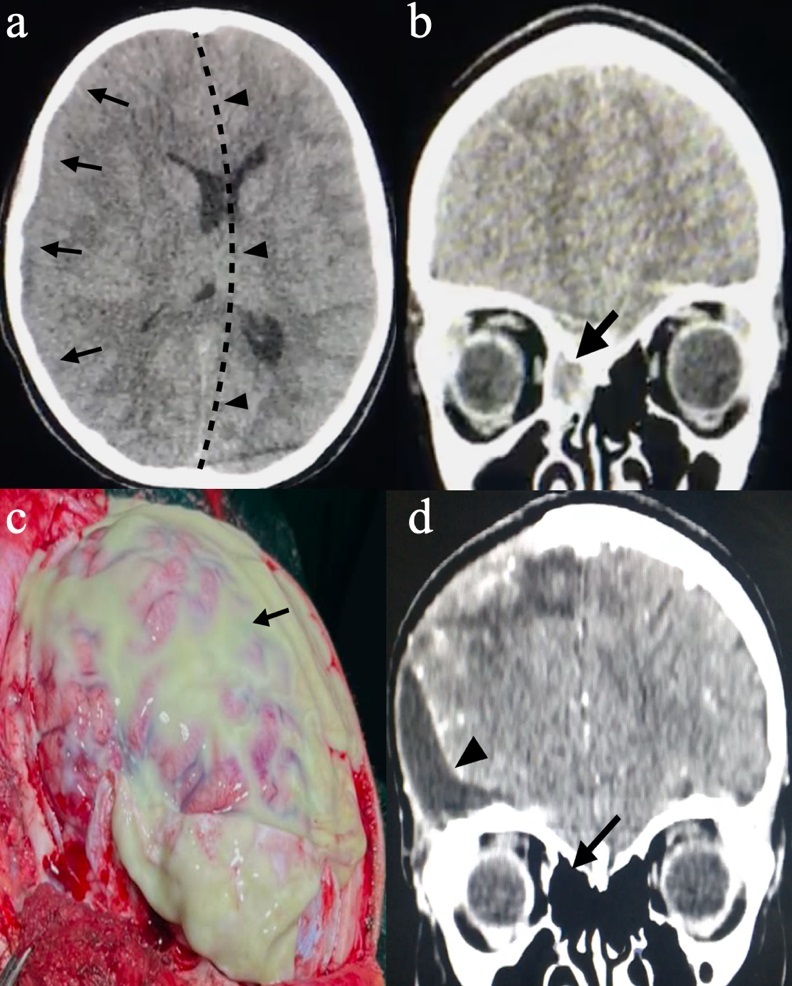

Adolescent, female, 12 years old, with a history of headache and vomiting, without fever, with progressive worsening and coma. Laboratory tests showed positive SARS-CoV-2 PCR RNA. She has not had the vaccine for COVID-19. A non-contrast-enhanced cranial tomography(Figure 1a) showed a right fronto-temporo-parietal cortical hypodense area with significant midline shift. A decompressive craniectomy was performed with drainage of extensive subdural empyema(Figure 1c).

Subdural empyema is most often a consequence of paranasal sinus infections. With the COVID-19 virus also located in the paranasal sinuses, it is not possible to determine whether it is a consequence or cause of subdural empyema (1). Although the pathophysiology is unclear, it is possible that upper respiratory infection by COVID-19 creates a favorable environment for bacterial sinusitis coinfection(Figure 1b), intracranial extension, and formation of subdural empyema (2). Another possible explanation is that the SARS-CoV-2 virus infection affects the immune system and makes the individual more susceptible to infection (3). Therefore, more studies are needed to clarify the relationship between SARS-CoV-2 infection and other infections.

Figure 1 (a) Computed tomography of the skull, with the axial section showing a right fronto-temporo-parietal hypodense area(black arrows) with significant midline shift(black arrowheads). (b) Computed tomography of the skull, with the coronal section showing signs of sinusitis with opacification of the right ethmoid sinus(black arrow). (c) Intraoperative view after opening the dura mater showing exposure of the right fronto-temporo-parietal cortex covered by viscous purulent secretion(black arrow). (d) Computed tomography of the skull, with the coronal section showing after treatment without ethmoid opacification(black arrow) and small postoperative CSF collection(black arrowhead).